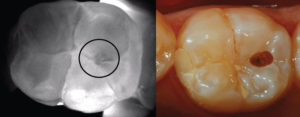

The CariVu device takes transillumination to a higher level. The device detects carious lesions and cracks interproximally, occlusally, and around cracks and restorations through near-infrared light. Dense enamel reflects this light while the porous carious lesions trap and absorb the light. As a result, CariVu produces an image where the healthy tooth appears light and the lesions dark. This results in accurate information without any ionizing radiation exposure.

Besides educating the patients, I know the CariVu image will provide the information I need to treat caries efficiently. CariVu illuminates both sides of the tooth simultaneously so I can see the size, shape and scope of initial carious lesions and around margins of failing restorations and plan excavation and treatment more effectively. Since I have this information before beginning treatment, it allows for smaller accesses and less invasive treatment. I can view fractures and related caries better with NIR transillumination technology than on X-ray, which can be misleading due to issues like burnout or the wrong angle.